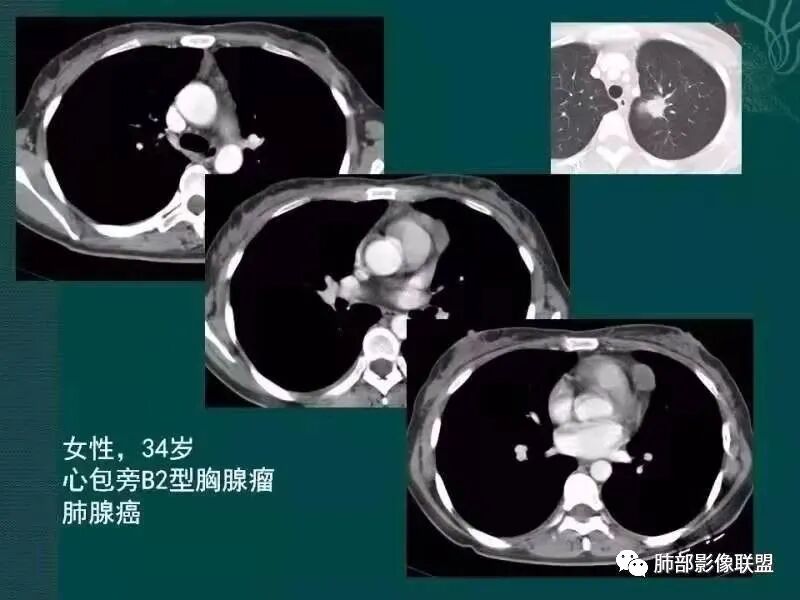

病史,老年女性,检查发现前上纵隔占位。

前上纵隔偏左侧实性病灶,边界清楚,边缘彭隆,浅分叶,内部密度均匀,未见钙化、脂肪密度,周围脂肪间隙清晰。

包膜完整,纤维分隔,结节感明显

平扫密度较均匀,增强渐进性不均匀强化,内见低密度纤维分隔。未见肿大淋巴结。未见胸腔积液。

肿块边界清楚,低密度纤维间隔,未见侵犯转移及增大淋巴结,多见于胸腺瘤AB型